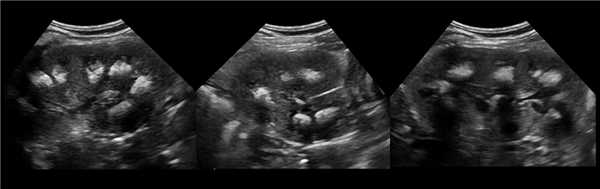

Рисунок. На УЗИ в уретероцеле определяется гиперэхогенная структура с акустической тенью — камень. Уретероцеле может являться одним из факторов, способствующих камнеообразованию.

Рисунок. На УЗИ округлое образование разделяет почечный синус на два сегмента с общей лоханкой; междолевые артерии огибают образование; эхогенность и интенсивность сосудистого рисунка внутри близка корковой зоне. Заключение: Гипертрофия колонны Бертини или неполная паренхиматозная перемычка. Это вариант нормального строения почки. Термин «неполное удвоение ЧЛК» неверный, т.к. неполная паренхиматозная перемычка не является признаком удвоения ЧЛК.

Рисунок. На УЗИ синус почки разделяет полная паренхиматозная перемычка (1, 2). В таких случаях разграничить удвоение почки от гипертрофии колонны Бертини поможет экскреторная урография. Удвоенная почка покрыта общей фиброзной капсулой. Полное удвоение предполагает наличие двух лоханок, двух мочеточников и двух сосудистых пучков. Неполноудвоенная почка (3) питается одним сосудистым пучком, мочеточник может быть удвоен вверху и впадать в мочевой пузырь одним или двумя устьями. Удвоение ЧЛК и мочеточников — фактор риска развития патологии (пиелонефрита, гидронефроза и др.).

Рисунок. На УЗИ синус почек широкий, неоднородной эхоструктуры (1, 2). На фоне гиперэхогенного жира гипоэхогенный очаг округлой формы (2), при ЦДК междолевые сосуды проходят через гипоэхогенную зону без смещения (3) — это гипоэхогенный жир. При ожирении липоматоз синуса можно ошибочно принять за атрофию паренхимы.